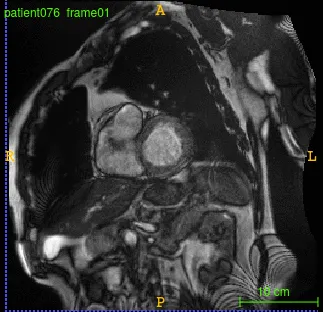

One of the complex and challenging diagnosis tasks involves cardiac cine Magnetic Resonance Imaging (MRI). Cardiac cine Magnetic Resonance Imaging (MRI) is primarily used for the assessment of cardiac function and diagnosis of Cardiovascular diseases (CVDs). Cardiac MRI is considered the most accurate method for the estimation of clinical parameters such as ejection fraction, ventricular volumes, stroke volume and myocardial mass. Cardiac cine MRI consists of images of the cross sections of the heart (entire heart can be covered) acquired at different time points during the cardiac cycle including end systole and end diastole. The diagnosis tasks consists of image segmentation to segment the left ventricle and derive quantitative measures to diagnose specific heart conditions.

- Image Pre-processing: Fourier analysis and circular Hough-transform for the region of interest (ROI) cropping

Input Image